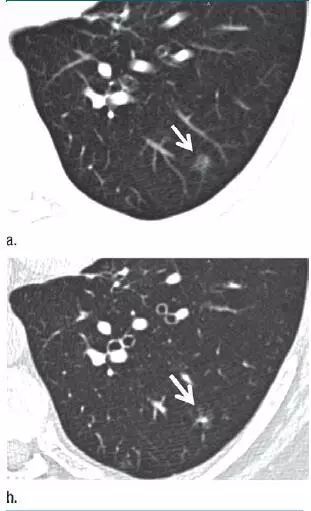

3. 可疑部分实性结节

图 3(a)层厚 5 mm 的 CT 横断面图像,显示左肺下叶有明显的纯磨玻璃样结节(箭头)。(b)同一水平层厚 1 mm 的 CT 横断面图像,显示病变为一伴有囊性成分(箭头)的可疑部分实性结节。